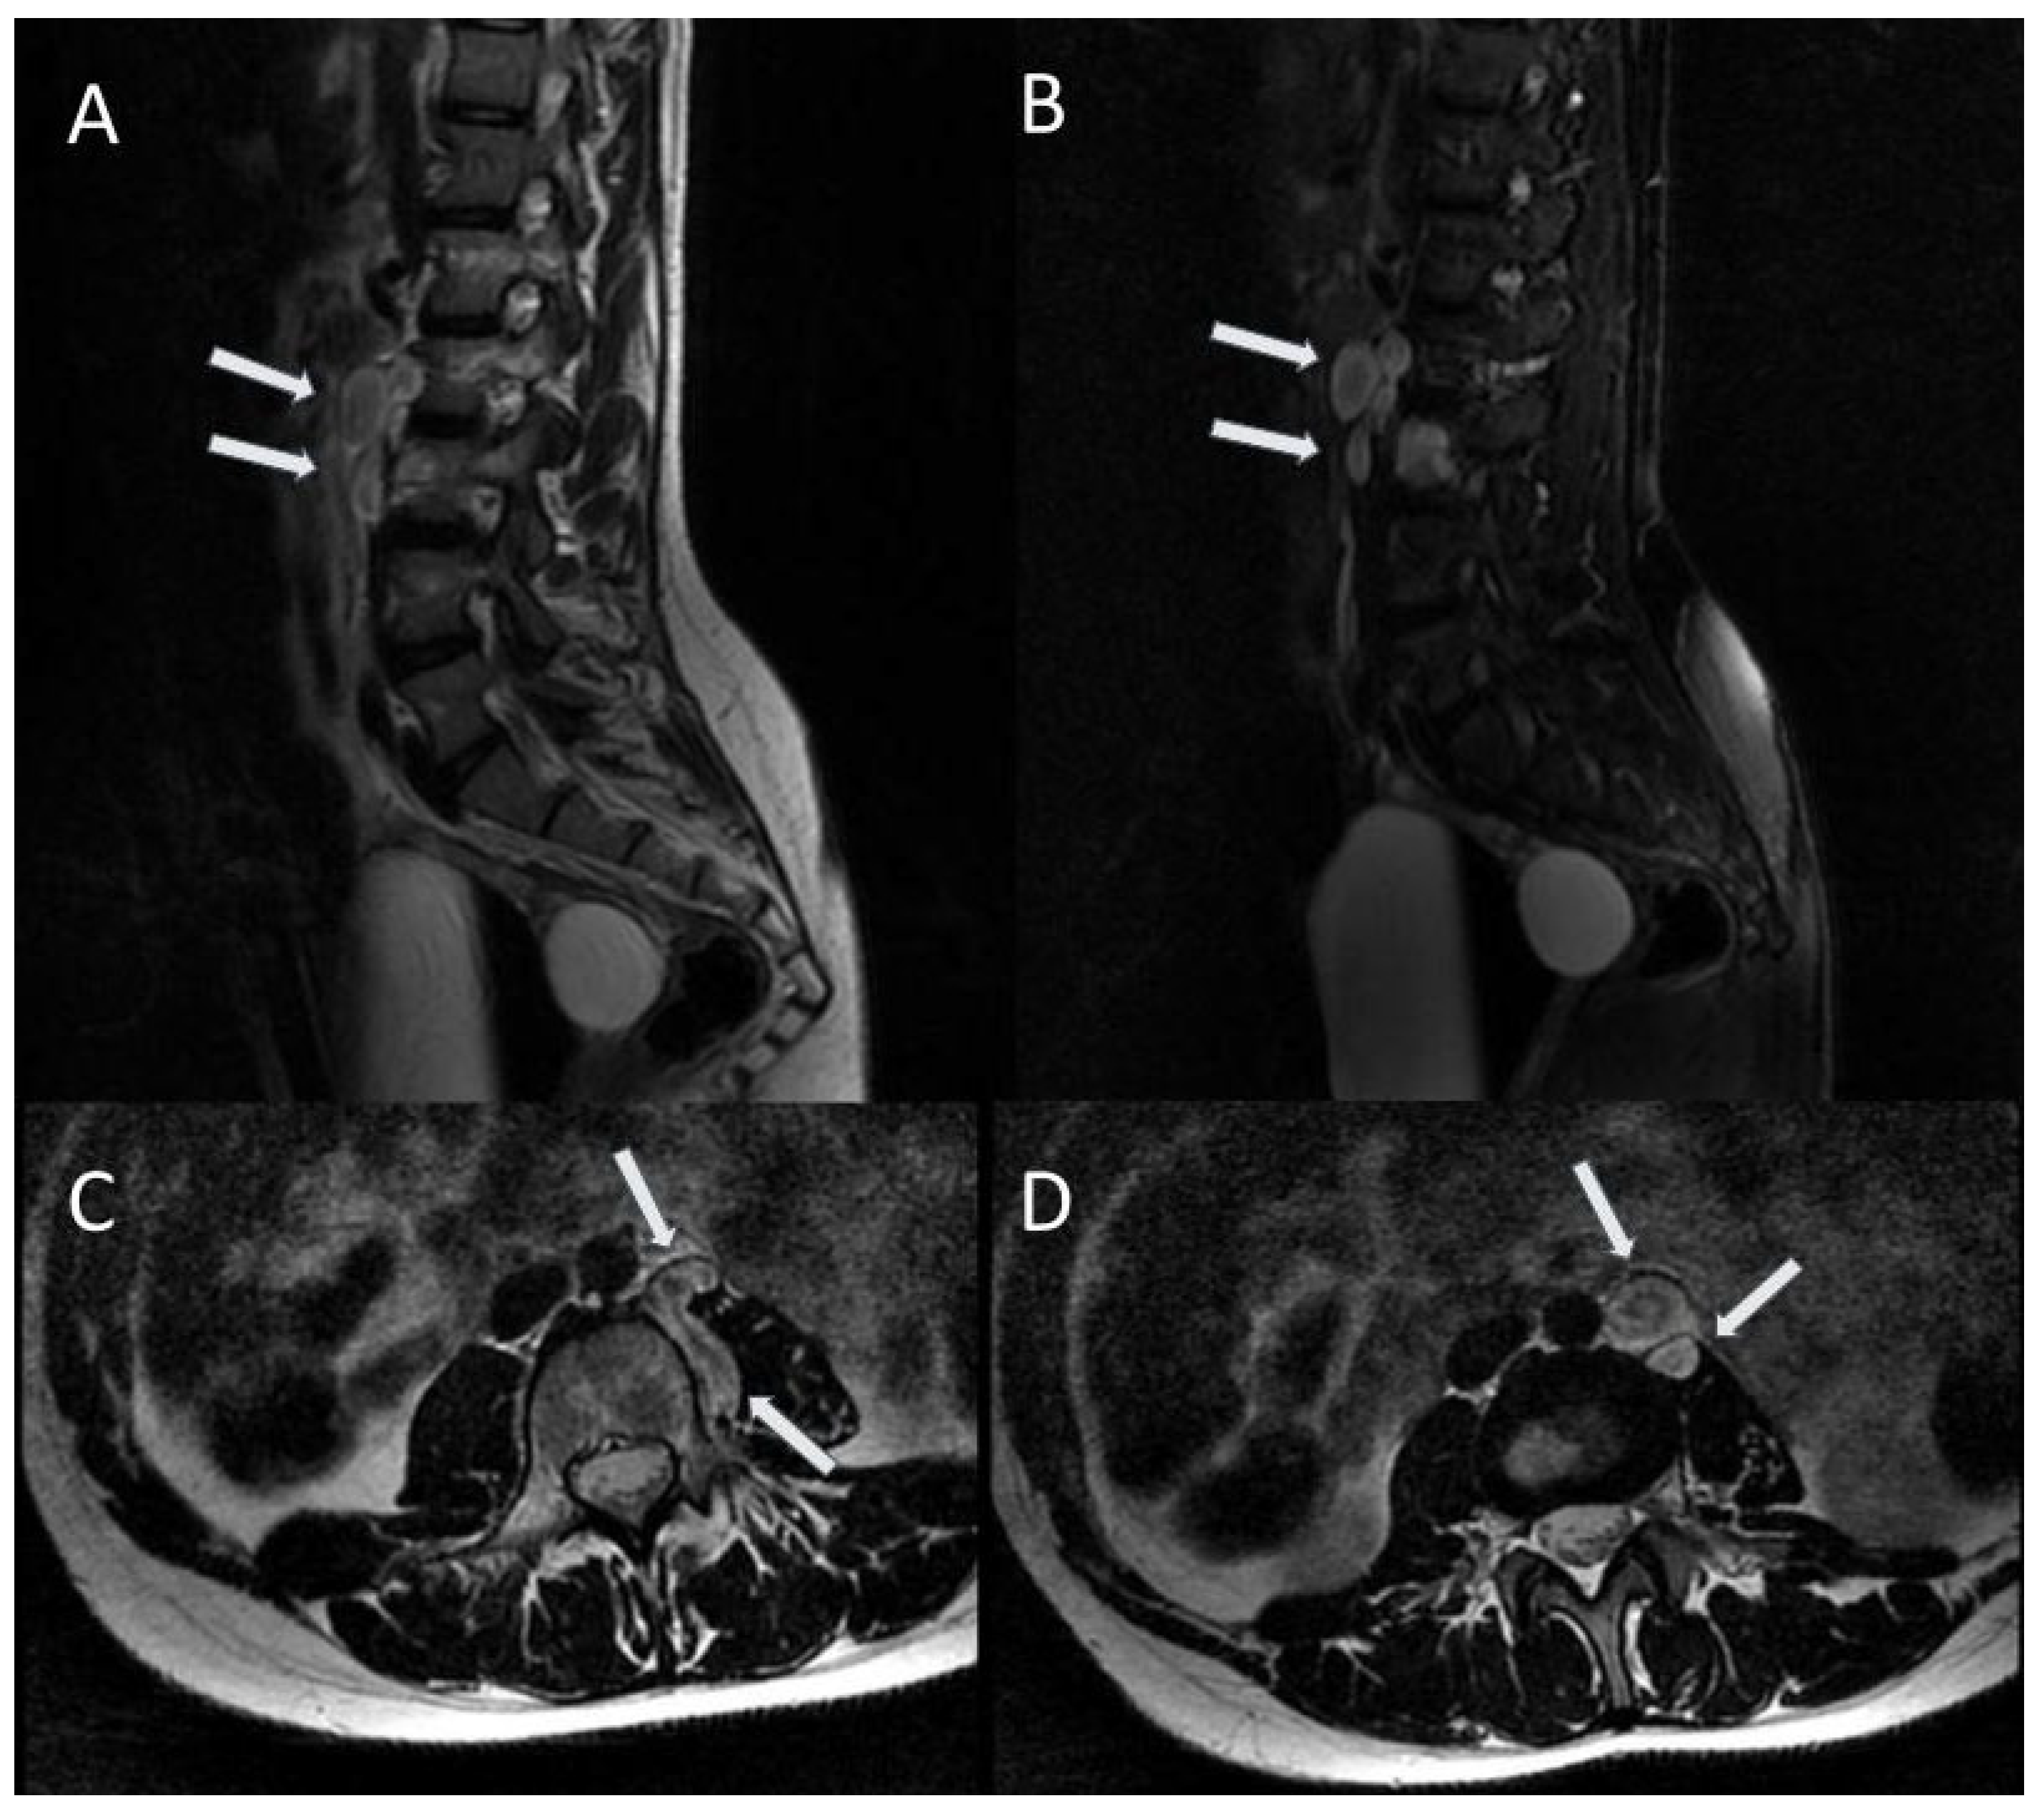

2.4. Spinal Tumours

| Spinal tumours: peripheral nerve sheath tumours and intramedullary tumours | 40–96% | Benign neurofibromas represent the majority of spinal tumours, while intramedullary lesions are rarely observed; |

| Neurofibromas usually show hyperintense signal on T2-weighted images with central hypointense target, and hypointense signal on T1-weighted images, with heterogeneous contrast enhancement. | ||

| Features suggestive of malignant nerve sheath tumour: enlarging tumour, tumour size > 5 cm, ill-defined margins, lack of a central hypointense target on T2-weighted images, heterogeneity with central necrosis. | ||